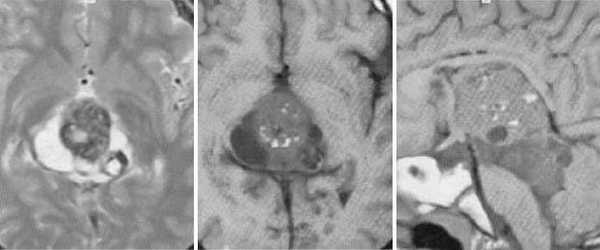

Пинеоцитома. На Т2 ВИ опухоль состоит из двух участков разной интенсивности МР-сигнала: высокой в передних отделах и низкой в задних. Четкость и линейность перехода свидетельствует о кистозном характере строения опухоли. Различия интенсивности МР-сигнала от жидкости в передних и задних отделах опухоли обусловлены эффектом «седиментации» белковых компонентов (вероятнее компонентов крови), опускающихся вниз при положении головы пациента на затылке.